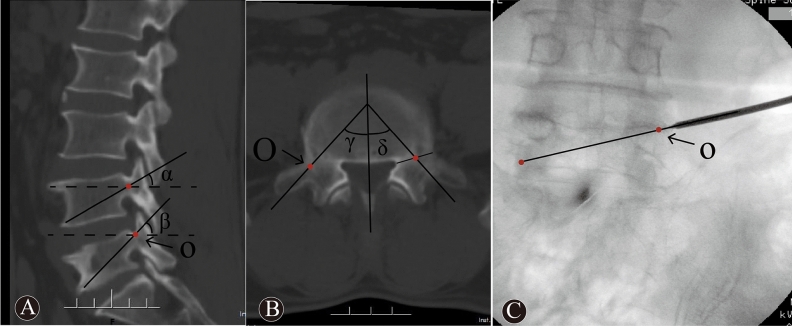

Figure 1.

Images showed the puncture approach via point “O” and TPA. The sagittal CT image (A) was showed that α and β were sagittal puncture angle of T-PKP and O-PKP, respectively. The cross-sectional CT image (B) was showed that γ and δ were transverse puncture angle of O-PKP and T-PKP, respectively. The X-ray image (C) was showed the puncture approach of O-PKP.

The O-PKP group: The O-PKP used a modified unilateral extrapedicular puncture approach. The bone entry point was the intersection between the base of the transverse process, the posterior-superior margin of the pedicle, and the lateral margin of the superior articular process. This entry point was defined as the “O” point (as this point was similar to the coordinate origin), as shown in Fig. 1A–C. Once the puncture needle reached the “O” point, it was close to the superior margin of the pedicle and was lateral to the superior articular process on lateral imaging (Fig. 2B). The puncture angle was adjusted such that the puncture needle entered the “O” point and the vertebral midpoint to the contralateral inferior corner of the vertebral body (Fig. 2A). The needle was then inserted slowly, using the anterior one-third midpoint of the vertebral body, as shown on lateral imaging, as the needle target. Posteroanterior imaging indicated that the needle had reached the vertebral midline. Lastly, a balloon was embedded in the vertebral body, and bone cement was then injected into the fractured vertebral body (Fig. 2C, D).

Preoperative plain radiographs, three-dimensional reconstructed CT images, and magnetic resonance images were obtained for all patients. In addition, postoperative plain radiographs were also evaluated. The local Cobb angle was measured to determine the kyphotic deformity on lateral radiographs12. The anterior/middle/posterior height of the vertebral bodies (distance between the upper and lower endplates) was measured by the mean of the lateral radiographs (Fig. 4). The height of the fractured vertebral body was assessed as the vertebral compression ratio before and after the operation. The compression ratio was computed by the anterior vertebral height / posterior vertebral height (A/P) 100%, and the middle vertebral height /posterior vertebral height (M/P) 100%. The bilateral distribution on lateral imaging was considered satisfactory only when the bone cement was distributed evenly across the vertebral midline. It was also considered good when the anteroposterior distribution of the bone cement on preoperative imaging was well distributed across the anterior one-third midline of the vertebral body13. The sagittal and transverse angles were measured on three-dimensional reconstructed CT images (Fig. 1A-B).